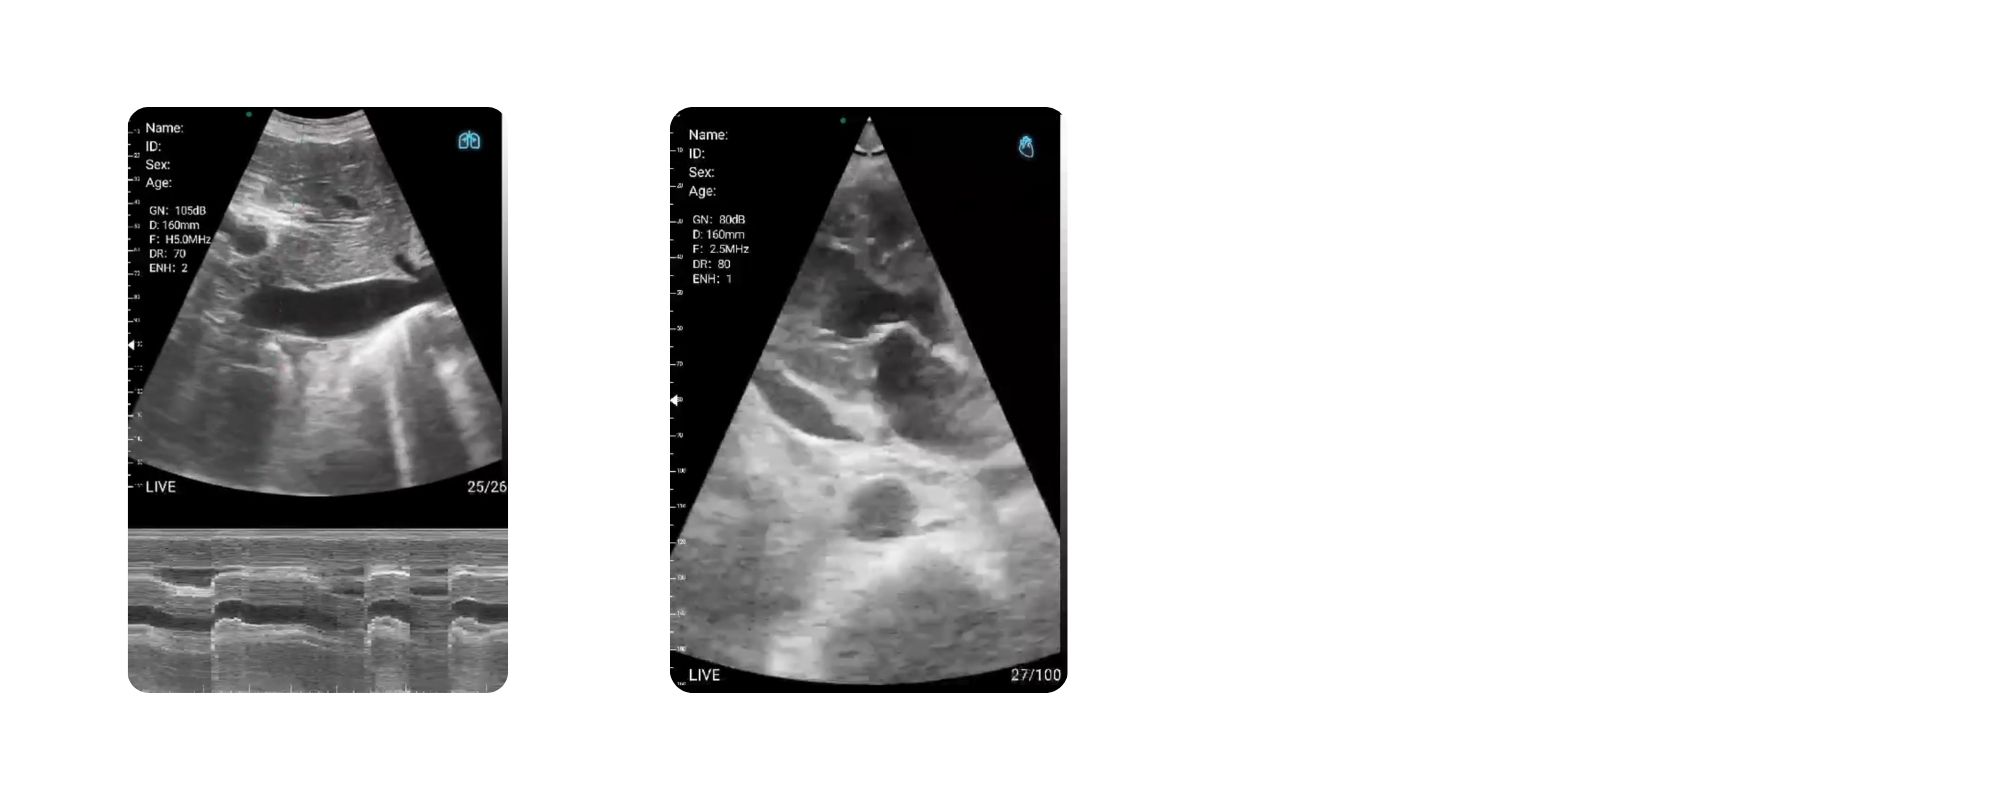

2. قلب و عروق (Cardiology & Vascular)

سونوگرافی هندهلد CLP4 برای کاربردهای قلبی بسیار مؤثر است و کاربردهای زیر را پوشش میدهد:

-

تصویربرداری چهار حفره قلب (4CH View)

بررسی حرکات دیوارههای قلب (برای تشخیص اختلالات حرکتی مانند Hypokinesia)

ارزیابی افیوژن پریکارد

بررسی پمپینگ قلب، EF اولیه

سونوگرافی داپلر جهت بررسی عروق محیطی و مرکزی

بررسی وریدهای اندامها برای DVT

6. ریه و پزشکی داخلی

این دستگاه برای متخصصین ریه و داخلی نیز بسیار کاربردی است:

تشخیص پنومونی

بررسی خطوط B و ارزیابی ادم ریه

شناسایی سریع افیوژنهای پلور

بررسی دیافراگم و عملکرد تنفسی